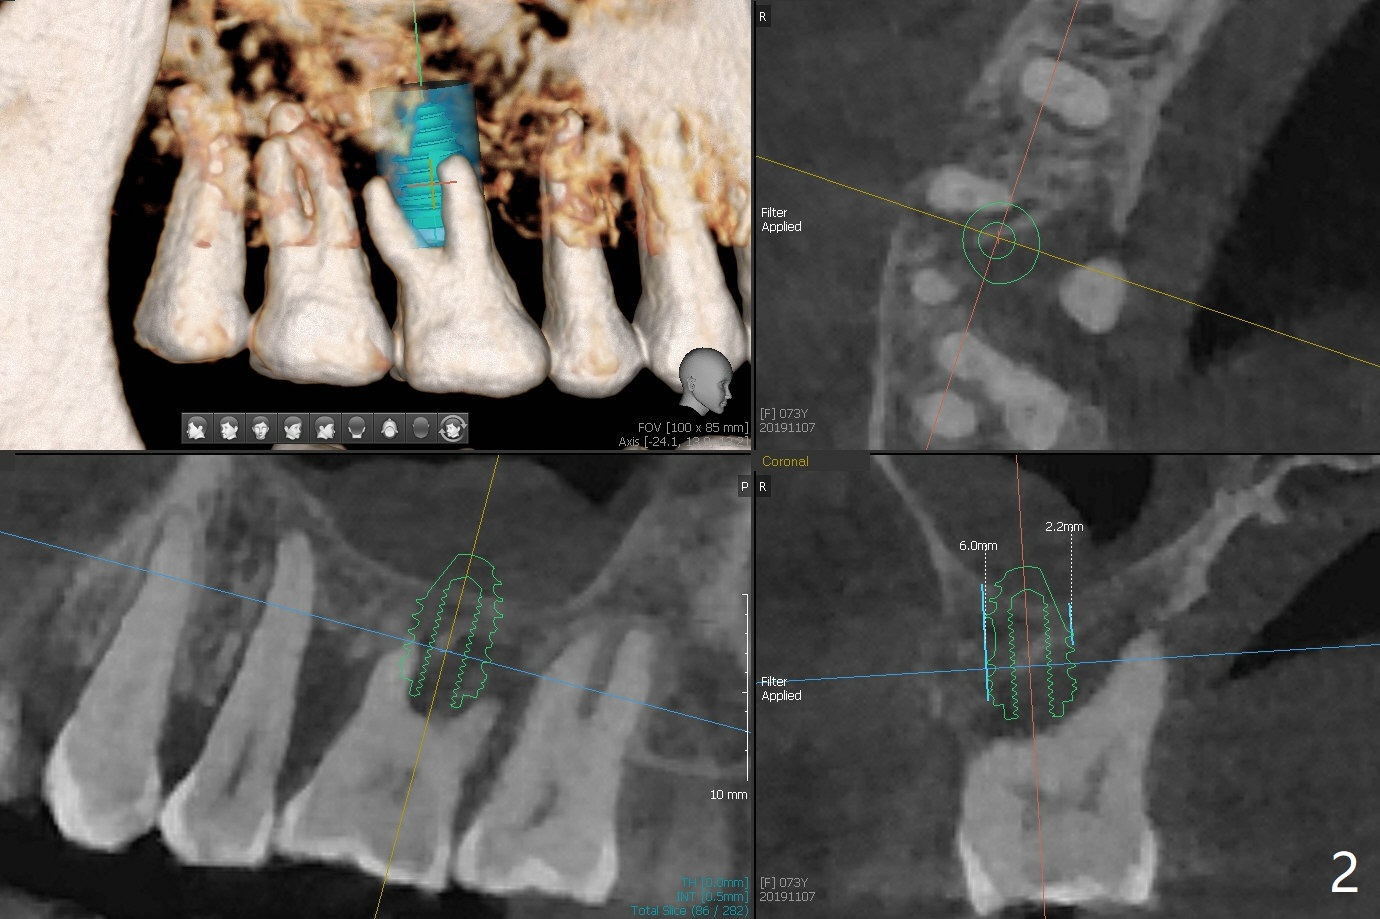

A 73-year-old woman with controlled diabetes has cold and hot sensitivity of the tooth #3. Although the bone loss is striking (Fig.1), mobility is I with the deepest pocket DL ~6 mm. Endo ice induces pain. Extraction and guided immediate implant appears to be the best option (Fig.2 (5x7mm FC)). Note the bone height (2.9 mm) and the thick sinus membrane (M, Fig.2') . B: buccal. Bony defect will be filled with sticky bone and held in place with Cytoplast, while PRF for sinus lift. Because she is afraid of implant, RCT, followed by SRP and possibly periodontal surgery, seems to be viable because of the straight, not-so-narrow canals (Fig.3-5). Due to time constraint, immediate implant will be done free hand. Use IS cassette, since there are 3 and 4 mm stoppers. Prepare FC dummy and water lifter for sinus lift.